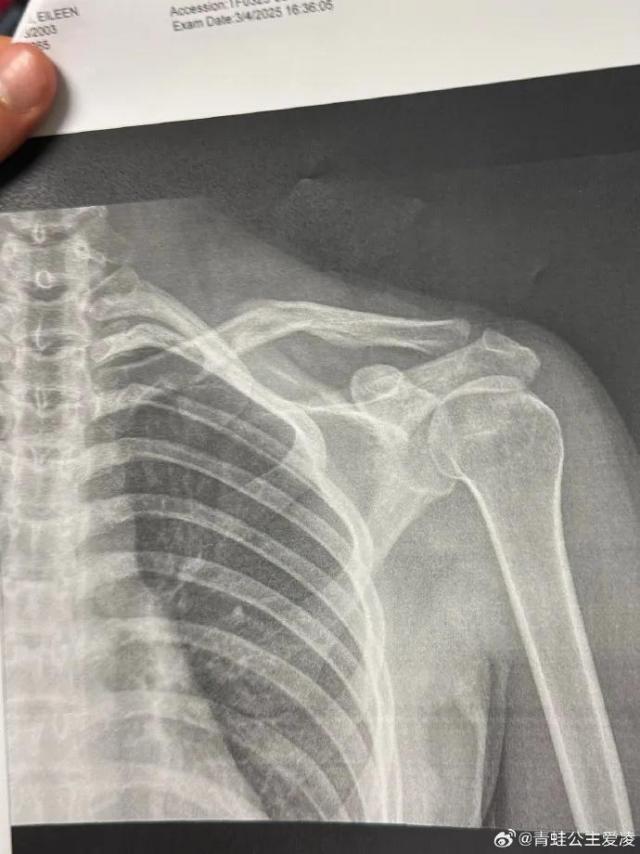

谷爱凌晒骨裂X光,此前因伤退出亚冬会。

3 月 9 日本,中国自由滑雪运动员谷爱凌在社交媒体上晒出肩部骨折。 X 相片,配上心痛的表情,随后相关话题登上热搜。

X 照片显示的日期是 3 月 4 日本,目前还不知道谷爱凌这次的伤是新伤还是旧伤。